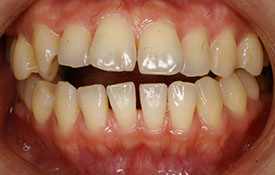

インビザラインの治療例:CASE-1

| プロフィール | 42歳 女性 |

| 所見 | 他院で行われた矯正歯科治療後の後戻りに悩まれて来院されました。 アイライナーの装着は、1日平均20時間ほどでした。 |